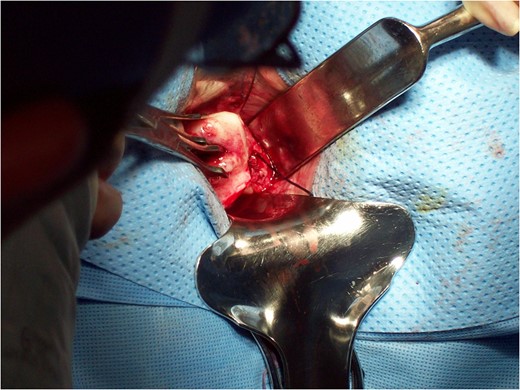

Vaginal examination was then done to place the speculum into the vagina and put a single tooth tenaculum on the anterior lip of her cervix and an Acorn uterine manipulator at the cervix to use for manipulation of the uterus during the laparoscopic portion. Repositioning the patient for the laparoscopic approach through the SPA, the infundibulopelvic ligament, round ligament, fallopian tubes and ovaries were first divided. The broad ligaments were dissected down to the level of the uterine arteries to mobilize the structures. Hysterectomy and bilateral salpingo-oophorectomy were then completed vaginally (Figs

6 and

7). The vaginal cuff was closed by baseball stitches first then with running interlocking stitch of chromic. The cuff was closed from the superior angle to inferior angle and the uterosacral ligaments were approximated to help with vaginal vault support.

Figure 6:

Dissection of uterosacral ligament vaginally.